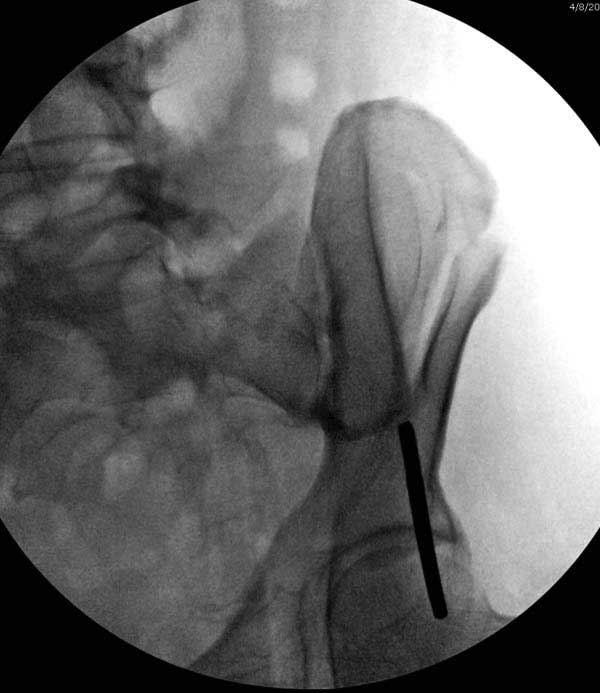

Здесь представлен случай 38 летнего больного (падение с высоты 9 метров) с нарушением тазового кольца. При поступлении для стабилизации передне-нижний аппарат наружной фиксации и на 6й день, вчера, операция из двух доступов.

Представлены снимки техники проведения стержней. Через место прикрепления прямой мышцы в Inferior Iliac Spine в направления вырезки создается жесткость. Weber clamp изнутри таза для репозиции, и фиксация после репозиции перелома крыла подвздошной кости. Наружный аппарат удален, нагрузка предполагается через два месяца.